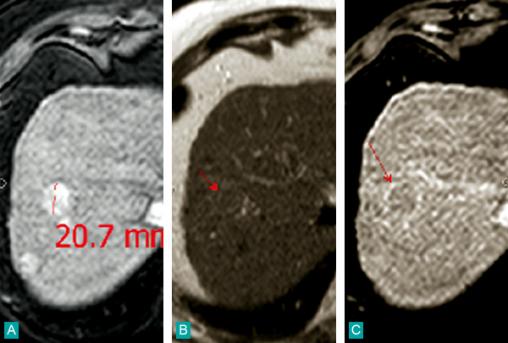

La Revue du Praticien - Jean-Frédéric Blanc IRM. A. Nodule hypersignal T1 spontané hyper-artérialisé ; B. Hyposignal T2 ; C. Wash-out au temps tardif.